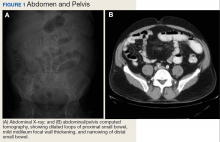

A physical examination revealed a distended abdomen with mild tenderness. He had no inguinal or ventral hernias. He also had no abnormal skin lesions. A rectal examination did not reveal any masses or blood. His laboratory values were normal. X-ray and computed tomography (CT) scan revealed dilated loops of proximal small bowel, mild wall thickening in a segment of the midileum, and narrowing of the distal small bowel suggestive of a partial small bowel obstruction (Figure 1). A 1-cm nonspecific omental nodule also was seen on the CT scan, but no enlarged lymph nodes or mesenteric calcifications were seen. There was no thickening of the terminal ileum.